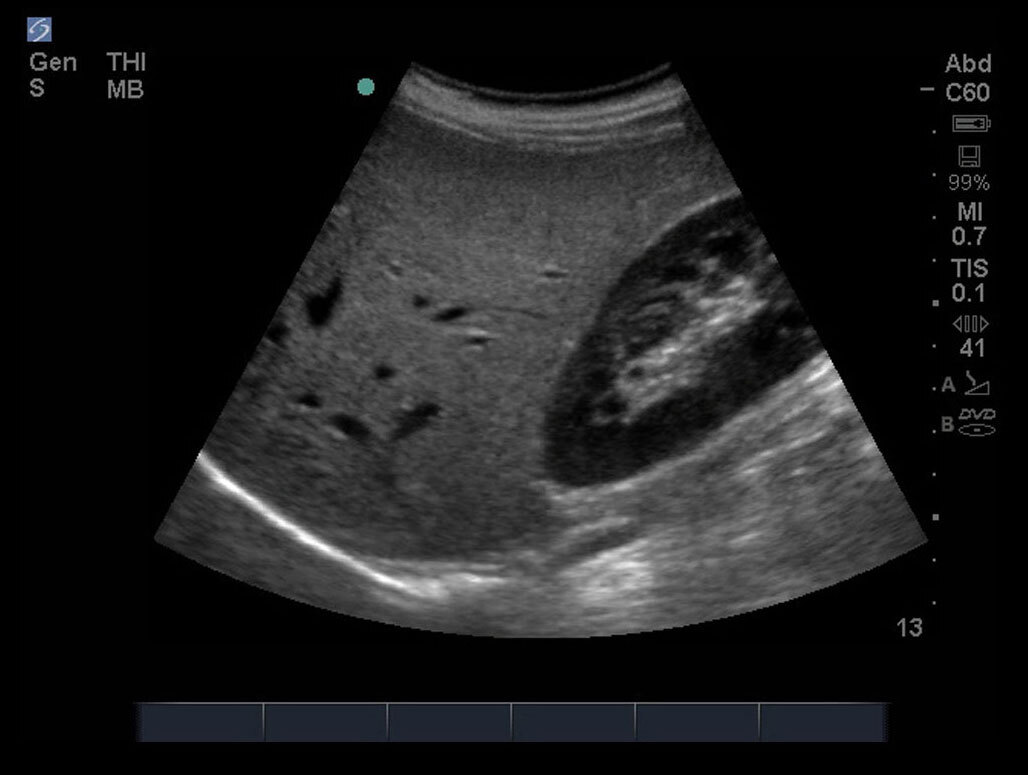

FAST Right Upper Quadrant (RUQ) 5 Image

M-Turbo.